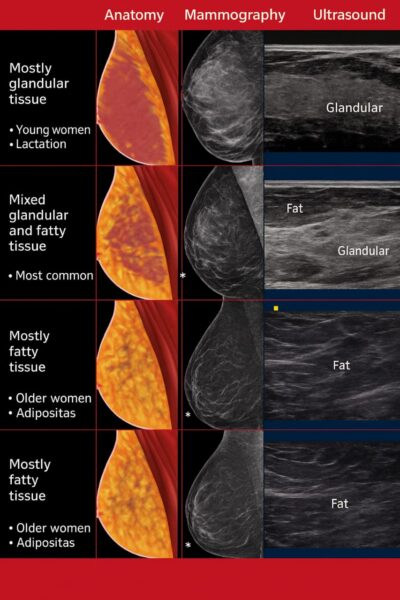

Mammography